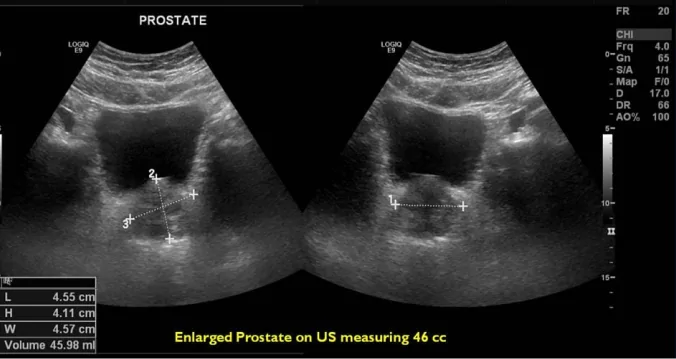

A transrectal ultrasound is a key diagnostic procedure for BPH, utilizing sound waves to create detailed images of the prostate gland. This non-invasive test allows physicians to evaluate prostate size and detect any abnormalities.